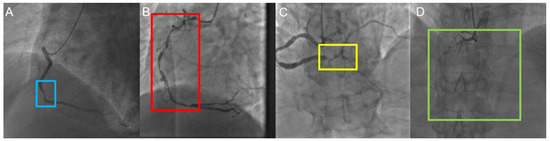

2.2. Reference Standard and Annotation Procedures

2.4.2. The Grad-CAM Technique